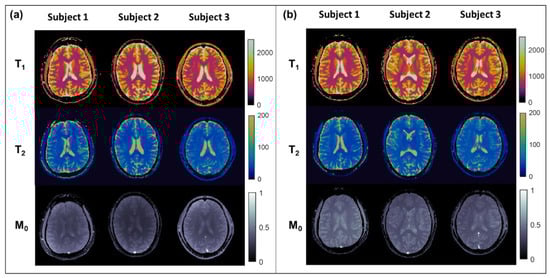

3.2. In Vivo Experiments